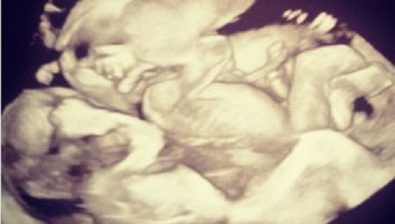

25 Weeks Pregnant: With Twins

Although your babies are floating around inside of you very comfortably, you might feel the exact opposite of comfort.

Things like heartburn, hemorrhoids, constipation, and even issues with bladder control might be driving you up the wall. And for good reason, too!

Please know that you’re nearing the home stretch and these annoying and uncomfortable symptoms won’t last forever. Steady on, mama!